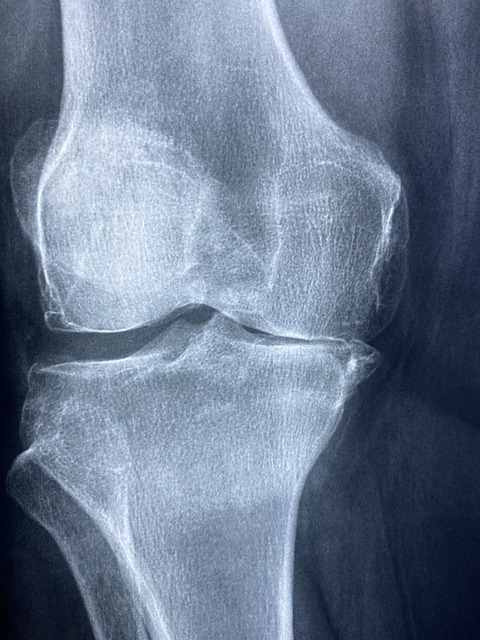

퇴행성 관절염 또는 골관절염의 주요 원인 중 하나는 자연적인 노화 과정입니다. 시간이 지남에 따라 관절이 마모되고 찢어지면 연골(뼈 끝을 완충시키는 보호 조직)이 점진적으로 파괴됩니다. 수년간의 움직임과 활동으로 인해 더욱 악화된 이러한 마모는 연골의 매끄러운 표면을 침식하여 활막을 자극해 염증을 유발합니다. 또 다른 중요한 원인 중 하나인 관절 부상이나 외상은 관절부위에 지속적인 영향을 남길 수 있습니다. 스포츠 관련 외상이나 사고로 인한 부상은 관절 내 섬세한 균형을 깨뜨려 연골의 퇴화를 가속화할 수 있습니다.

퇴행성 관절염의 특징적인 초기 징후는 잠에서 깰 때나 일정 기간 활동 하지 않으면 관절이 뻣뻣해지는 것입니다. 아침 경직은 부드럽게 움직이면 30분 이내에 개선되는 경향이 있으며, 관절 운동 범위가 점차적으로 감소하여 구부리거나 무릎을 꿇는 것과 같은 특정 활동이 어려워집니다. 이 제한은 처음에는 감지하기 어려운 경우가 많지만 해결하지 않고 방치하게 되면 관절의 불편함이 더욱 진행될 수 있습니다.

퇴행성 관절염의 독특한 징후는 관절 간 마찰음의 출현입니다. 이는 영향을 받은 관절 내에서 연골이 마찰을 일으킬 때 삐걱거리거나 갈라지거나 터지는 듯한 느낌입니다. 이러한 움직임은 관절 내부 구조를 변화시키며, 흔히 무릎관절이나 슬관절에서 나타나는 경우가 많습니다.